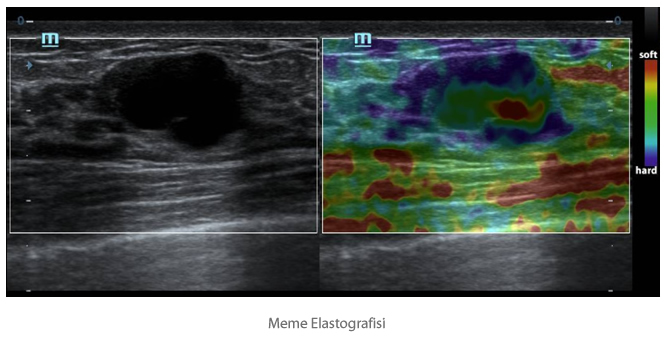

Natural Touch Elastografi

Mindray'in patentli en son teknolojisi temelli Natural Touch Elastografi, kullan?c? ?al??t?rma tekniklerine ba?l?l??? azalt?r, daha y├╝ksek klinik fayda i?in operat?r├╝n tekrarlanabilirli?ini geli?tirir.

- Daha y├╝ksek kat?l?k hassasiyeti.

- ?yi stabilite ve tekrarlanabilirlik.